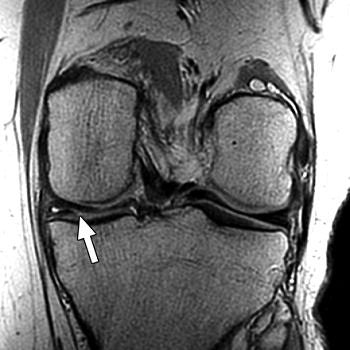

| Above, 27-year-old man with meniscal tear. Coronal 2D fast spin-echo (FSE) image (TR/TEeff, 4,000/38) shows tear (arrow). Middle, coronal 3D FSE extended echo-train acquisition (XETA) image (TR/TEeff, 2,500/38). Tear (arrow) was visible on two images of 2D FSE acquisition and 12 of coronal 3D FSE XETA images. Below, sagittal reformation of 3D FSE XETA dataset shows tear (arrow). |

Imaging at 3 tesla improved the resolution of 3D FSE XETA to 0.6-mm isotropic compared with 0.7-mm isotropic for 1.5-tesla images, the authors stated. In the volunteer with knee pain, 3D FSE XETA and 2D FSE revealed a meniscal tear in the posterior horn of the medial meniscus. Still, on the 3D FSE XETA, the tear was visible on a dozen images in the coronal plane versus two images from the 2D FSE acquisition.